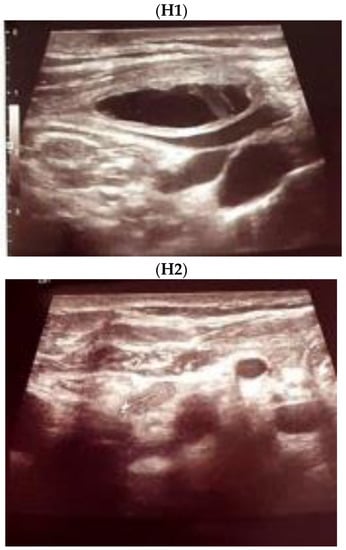

- Touska, P.; A Constantinides, V.; Palazzo, F.F. A rare complication: Lymphocele following a re-operative right thyroid lobectomy for multinodular goitre. BMJ Case Rep. 2012, 2012, bcr0220125747. [Google Scholar] [CrossRef] [PubMed]

- Ohta, N.; Fukase, S.; Suzuki, Y.; Ishida, A.; Aoyagi, M. Treatments of various otolaryngological cystic diseases by OK-4321: Its in-dications and limitations. Laryngoscope 2010, 120, 2193–2196. [Google Scholar] [CrossRef] [PubMed]